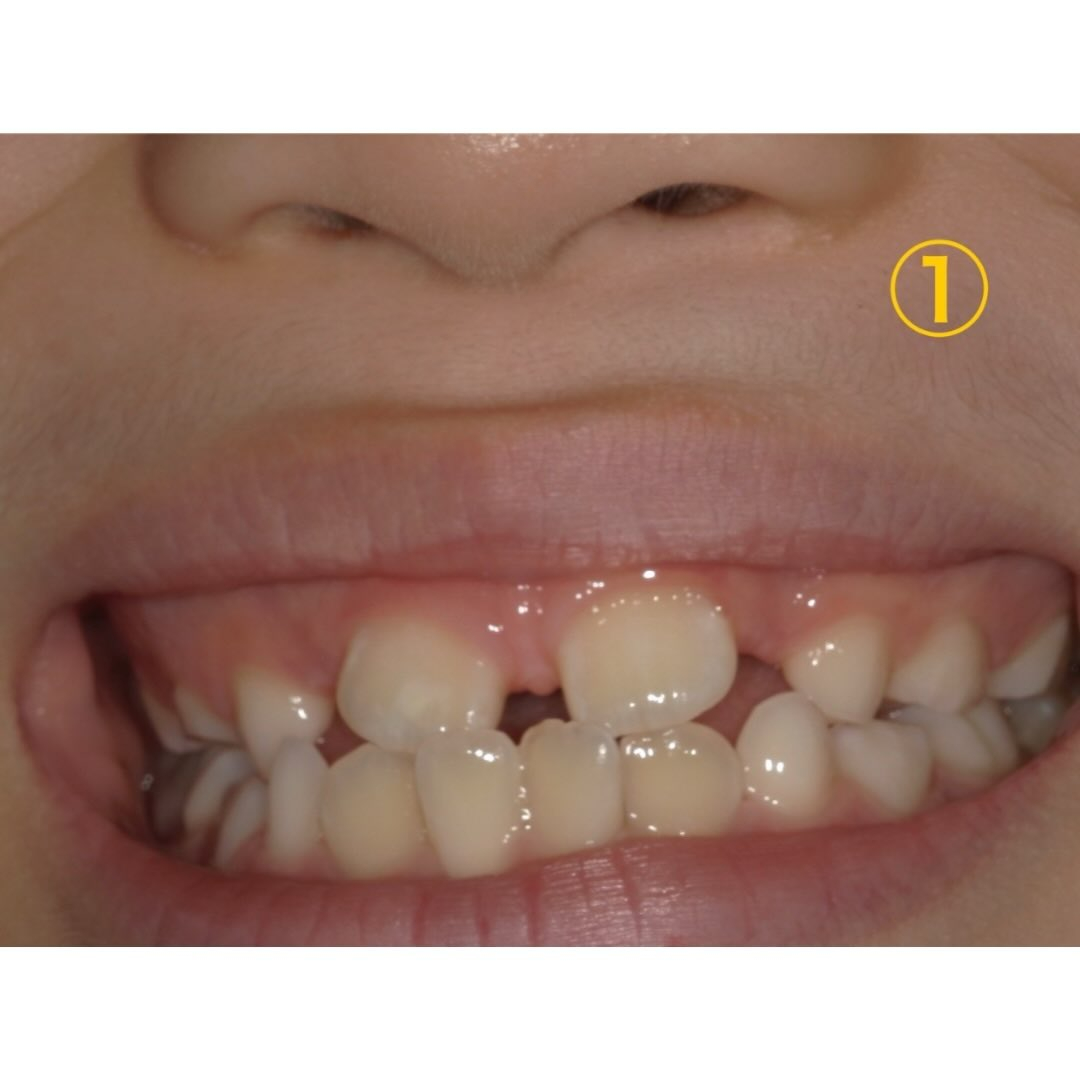

①〜③は1年ごとの1番変化が分かる写真を抜粋しました。

①、②の時は特に目立った汚れもなく生え変わりもあるので3ヶ月に1回定期検診を行っていました。